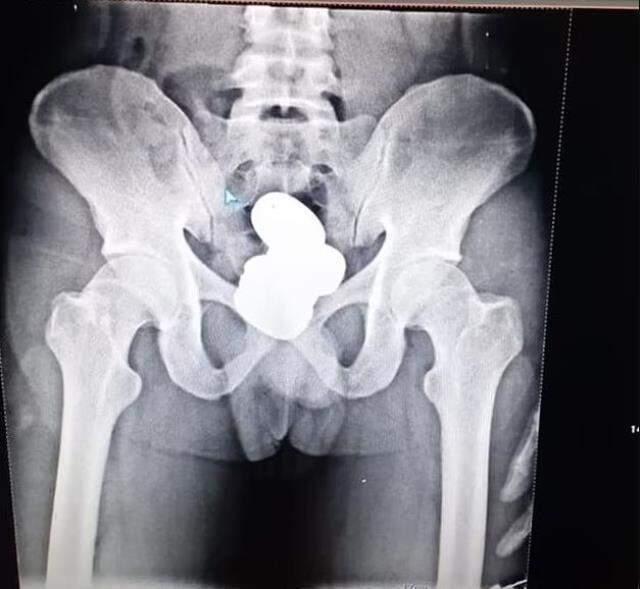

Özellikle düğün mevsimi yaklaştığında altın kaçakçılığının arttığı Hindistan'da bir kişi, toz haline getirdiği 850 gram altını dört kapsül halinde makatına yerleştirerek uçağa binmeye çalıştı. X-ray cihazının ele verdiği kaçakçıdan çıkan altının değeri ise 504 bin lira olarak belirlendi.

Hindistan'ın Manipur eyaletinden başkent Delhi'ye uçmak isteyen bir kaçakçıyı havalimanında bulunan X-ray cihazı ele verdi. Güvenlik güçleri tarafından gözaltına alınan Mohammad Sharif isimli şahsın makatında dört kapsül haline getirilmiş 850 gram ağırlığında toz altın bulundu.

Bir süre gözaltında tutulan Sharif, emniyet güçlerine karşı sessiz kalmayı tercih etti. Söz konusu dört kapsülün değerinin ise toplamda 42 bin pound, Türk parasıyla 504 bin lira olduğu belirlendi.